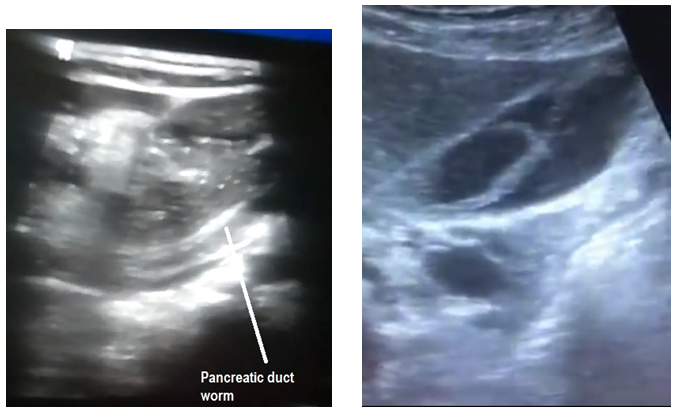

In 20 cases with biliary ascariasis observed with ultrasonography, there were 8 patients with gallbladder (Figure 1-2) and 7 with worms in the common bile duct (Figure 3-4). In 5 cases, the worms were found in the main hepatic duct (Figure 5-6) and pancreatic duct (Figure 7-8) and no case was seen with complicated intrahepatic abscess cavity. Ultrasound confirmed the dilatation in common bile duct as estimated about 10-20 mm, in 7 patients (Table 1 and Pie chart 1).

Figures 7-8 Pancreatic duct worm.